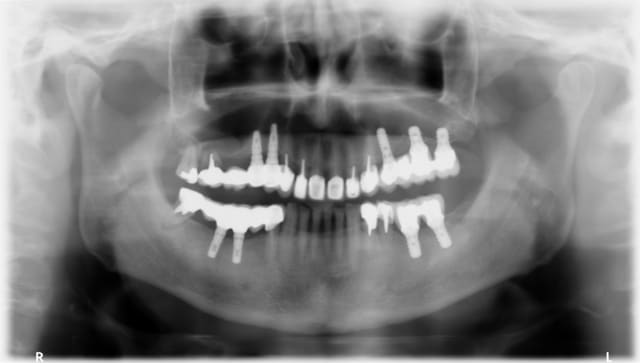

Un patient se présente avec le bridge secteur 1 mobile à cause de la fracture de 17. De plus, les piliers sont dévissés sur 14 et 15. Le patient n'a qu'une facture indiquant : pose de 2 implants dentaires.

Avez vous une idée de la marque des implants au vue de la pano, afin que je puisse commander le tournevis adequat ?

Ces implants me font penser à des BIOMET 3 I coniques connexion "certain".

pareil, biomet 3i...

http://whatimplantisthat.com/implant/osseotite-tapered-certain-2/